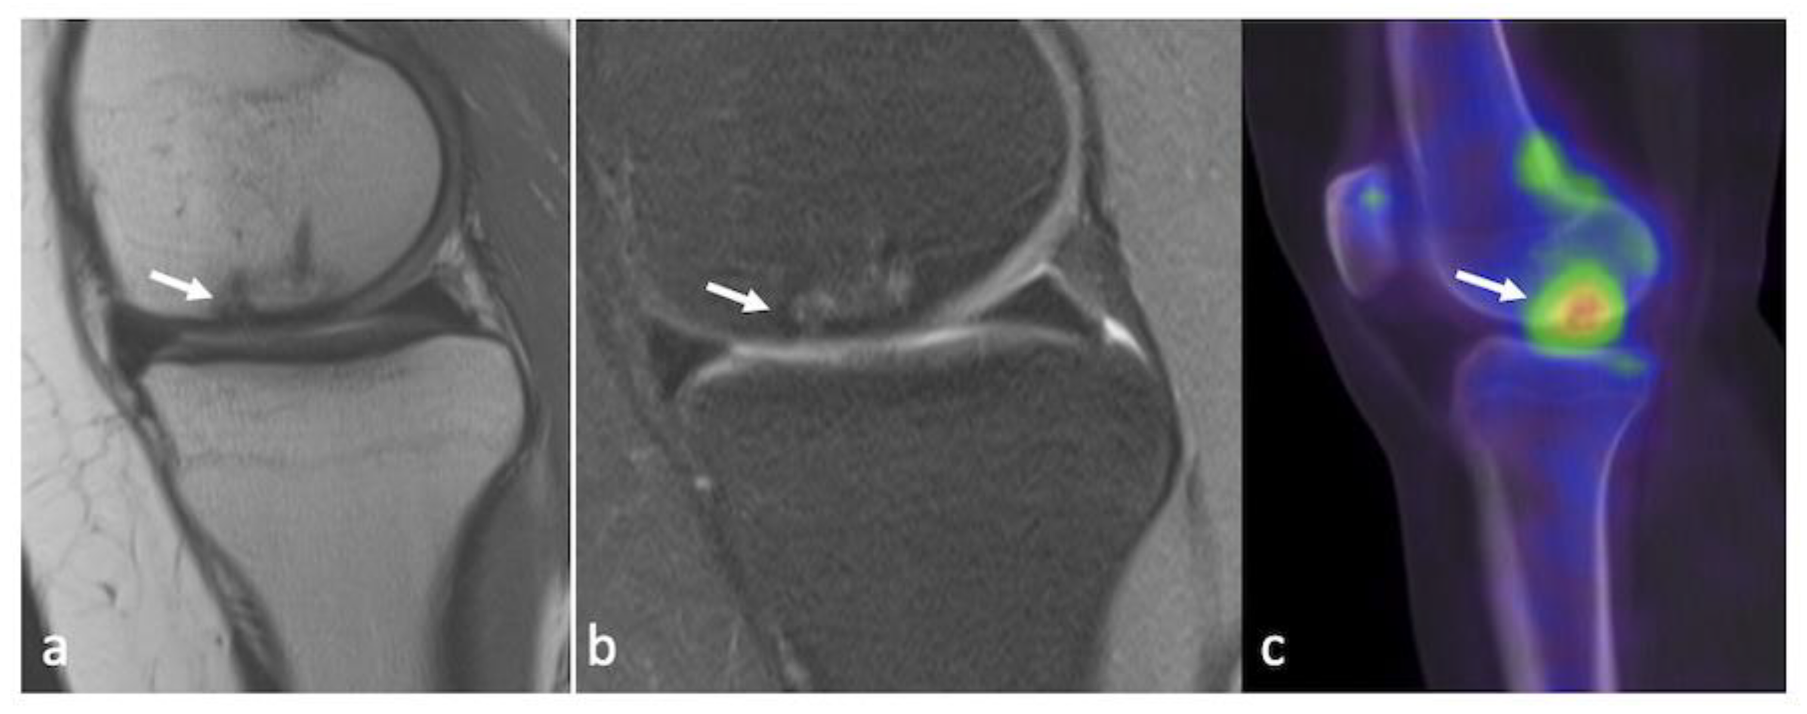

3.5. Integrated PET–MRI

- Nakamura, H.; Masuko, K.; Yudoh, K.; Kato, T.; Nishioka, K.; Sugihara, T.; Beppu, M. Positron emission tomography with 18F-FDG in osteoarthritic knee. Osteoarthr. Cartil. 2007, 15, 673–681. [Google Scholar] [CrossRef]

- Kobayashi, N.; Inaba, Y.; Tateishi, U.; Yukizawa, Y.; Ike, H.; Inoue, T.; Saito, T. New Application of 18F-Fluoride PET for the Detection of Bone Remodeling in Early-Stage Osteoarthritis of the Hip. Clin. Nucl. Med. 2013, 38, e379–e383. [Google Scholar] [CrossRef] [PubMed]

- Jena, A.; Taneja, S.; Rana, P.; Goyal, N.; Vaish, A.; Botchu, R.; Vaishya, R. Emerging role of integrated PET-MRI in osteoarthritis. Skelet. Radiol. 2021, 50, 2349–2363. [Google Scholar] [CrossRef]